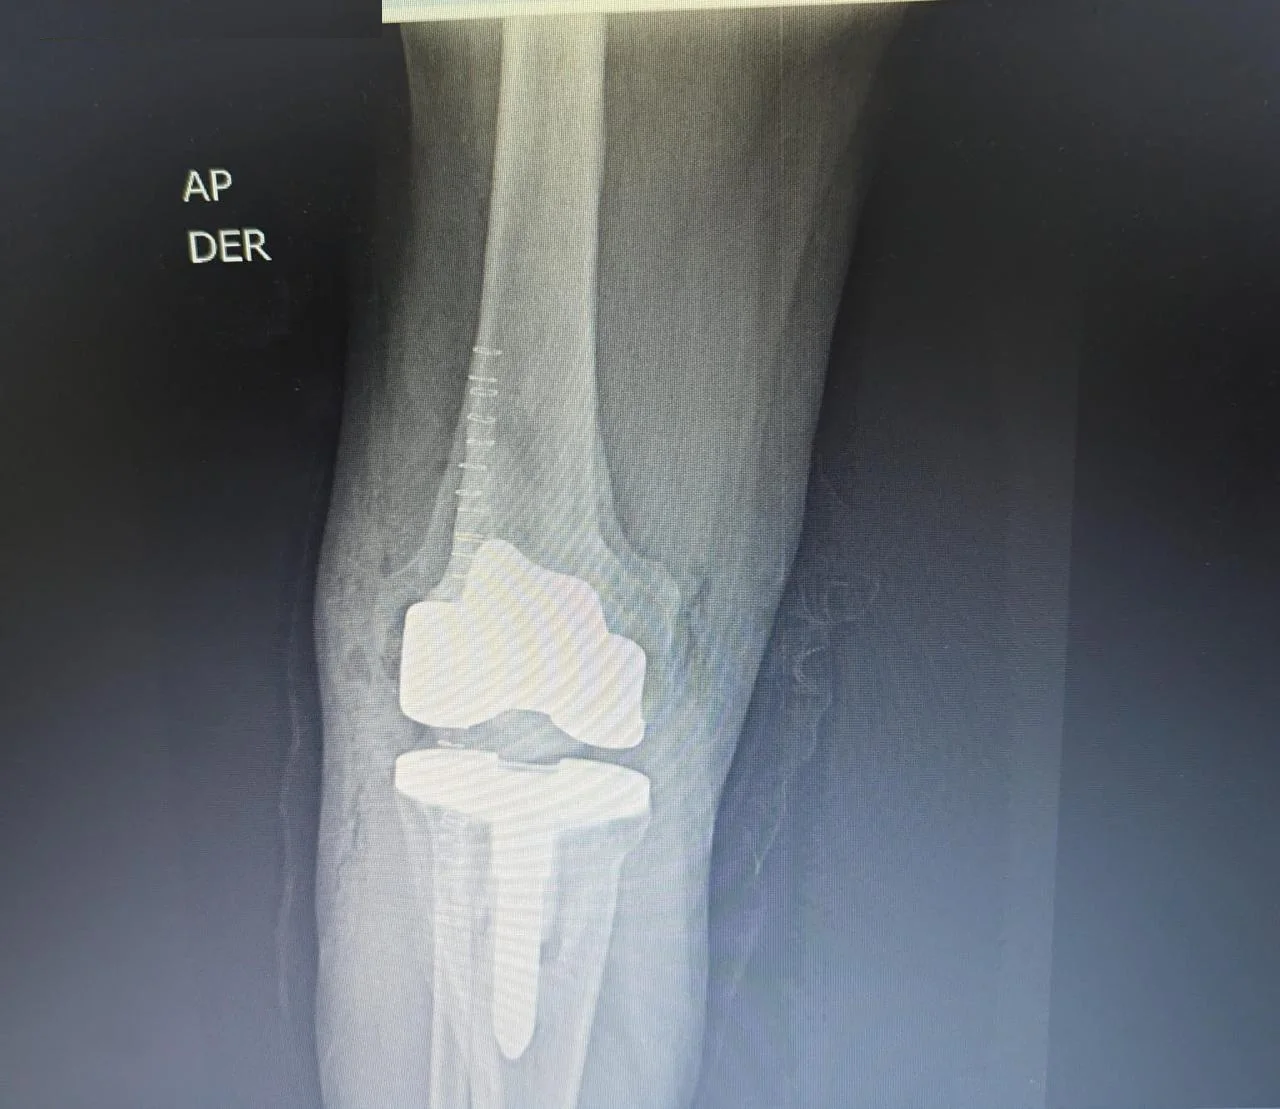

Después Radiografía postoperatoria de reemplazo articular de rodilla tras fractura de tibia

Traumatología

Reemplazo articular

Fractura de Tibia

• Perfil del Paciente: Masculino, 50 años.

• Historia Clínica: Antecedentes de 25 años de evolución con dolor crónico y pérdida de movilidad.

• Diagnóstico: Osteoartrosis secundaria a fractura de rodilla antigua.

• Resultado (Caso 2024): Intervención exitosa con recuperación completa. Actualmente el paciente presenta una evolución óptima y retorno a su vida cotidiana.